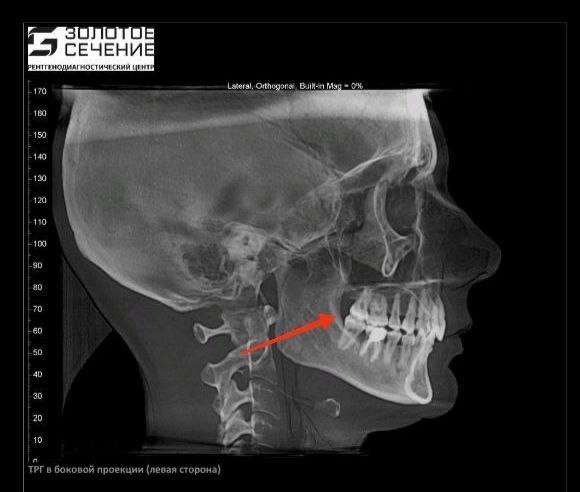

В чате курса девушка прислала снимки КТ стоя и МРТ лежа. Специалист сразу задала вопрос, что произошло, оказалось, просто положение тела разное.

К вопросу о том, почему нельзя регистрировать прикус лежа в кресле стоматолога, изготавливая в итоге под лежачее положение пломбы, коронки и прочие приблуды.

Это как и с зубами: лечить или сделать слепки удобнее, конечно, лежа - положение не имеет значения. Но именно для понимания истинной картины того, как челюсти и зубы стоят относительно друг-друга, требуется вертикальное положение.